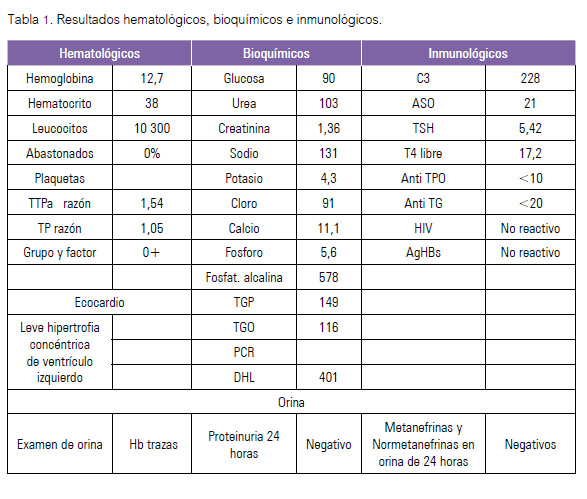

Ingresó dos días después al Servicio de Medicina D, con 60 kg de peso, 175 cm de talla, frecuencia cardiaca y respiratoria de 92 y 20 por minuto, respectivamente, y presión arterial 130/90 mmHg. El examen clínico no mostró otros hallazgos, salvo la disminución de ambos pulsos pedios. Los exámenes de laboratorio son presentados en la Tabla 1.

Se obtuvo angiorresonancia abdominal y cerebral seis días después del ingreso al servicio. Los hallazgos a nivel de aorta abdominal y arteria renal se presentan en las Figuras 1 y 2. No se encontraron alteraciones en arterias cerebrales.